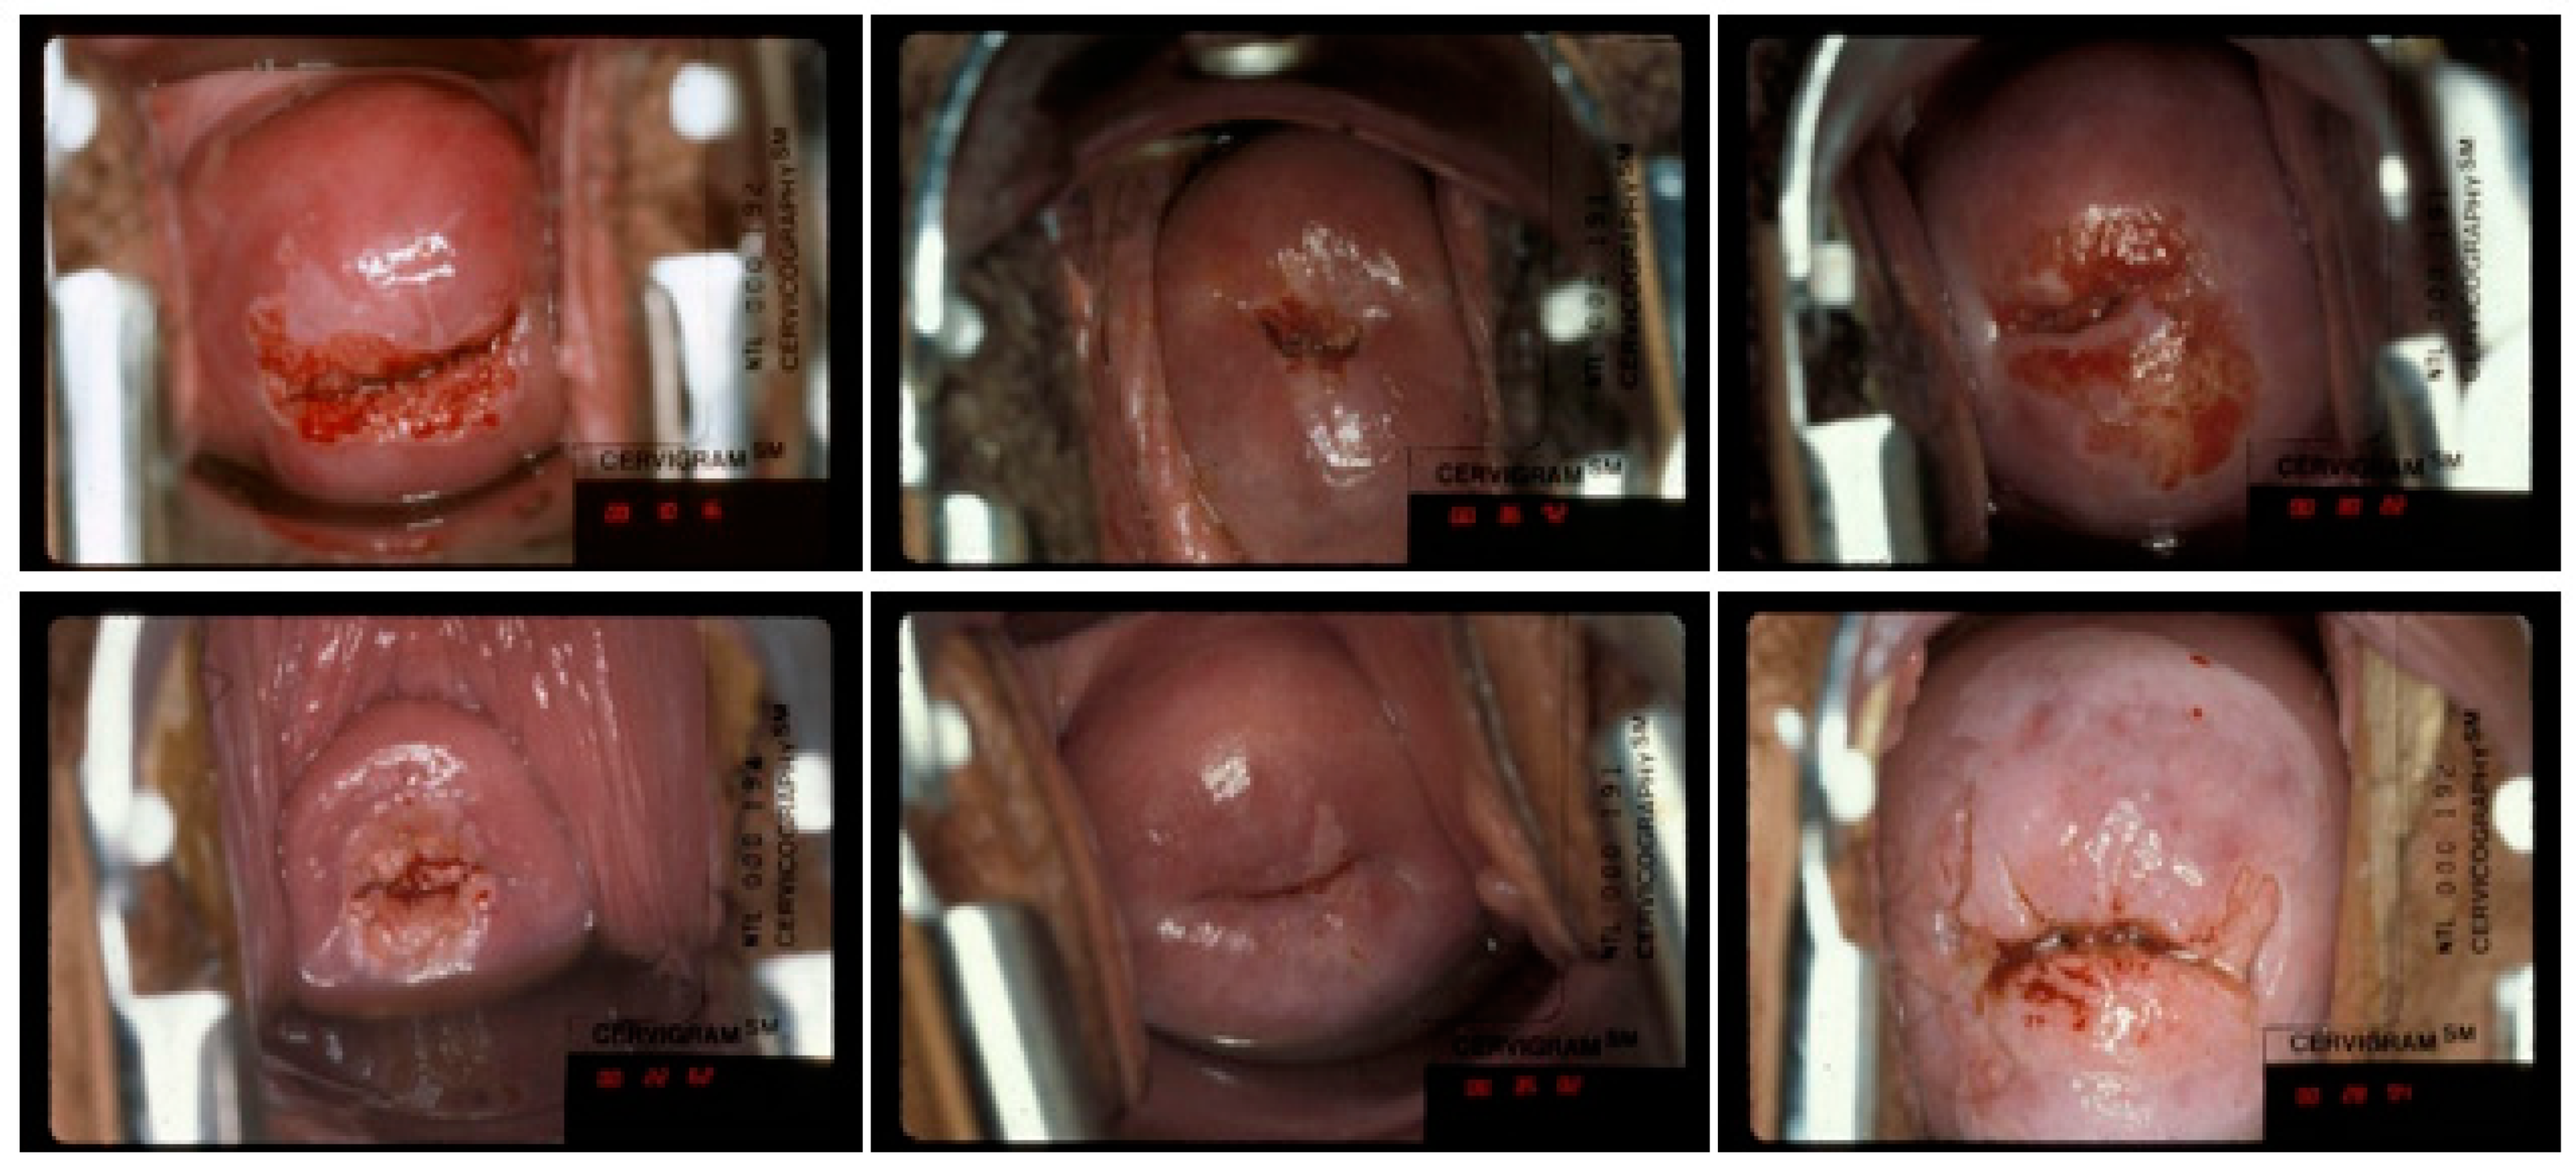

2. Image Data

4.3.2. Out of Region of Interest (RoI) and Insufficient Coverage

4.3.3. Inaccurate Ground Truth Label and Bad Image

4.4. Quality Degradation